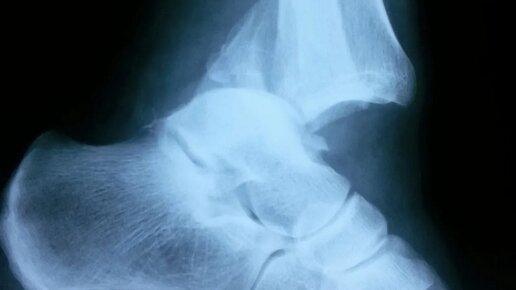

Перелом лодыжек

Ушибы и переломы в Москве: Перелом лодыжек — один из наиболее часто встречающихся видов травм, возникающий чаще в результате падения во время гололеда или при занятии спортом. Переломы лодыжек характеризуются нарушением анатомической целостности дистального отдела малоберцовой кости (перелом наружной лодыжки) или нарушением целостности дистального отдела большеберцовой кости (перелом внутренней лодыжки). Иногда так же говорят о переломе одной , двух и трех лодыжек. Трех лодыжек у нас нет. Просто...

Статья GHRS Перелом лодыжки - это нарушение целостности костей голеностопного сустава. Это может произойти из-за травмы, такой как удар, падение, или сдавливание. Переломы лодыжек бывают разными, но чаще всего они происходят с смещением или без смещения костей. Реабилитационный период после перелома лодыжки имеет свои особенности, которые зависят от тяжести травмы, возраста пациента, наличия сопутствующих заболеваний и индивидуальных физиологических особенностей. Вот некоторые ключевые аспекты, которые...